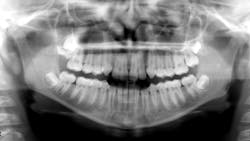

Healthy 11- (figure 1) and 14-year-old (figure 2) males present to the office for new-patient exams. Clinically, it was noted that the eruption patterns were not as they would typically be, primarily for the second molars in the 14-year-old. A panoramic radiograph was taken, revealing large radiopacities around the second molars on the right side. Both patients reported lack of pain upon palpation in these areas.